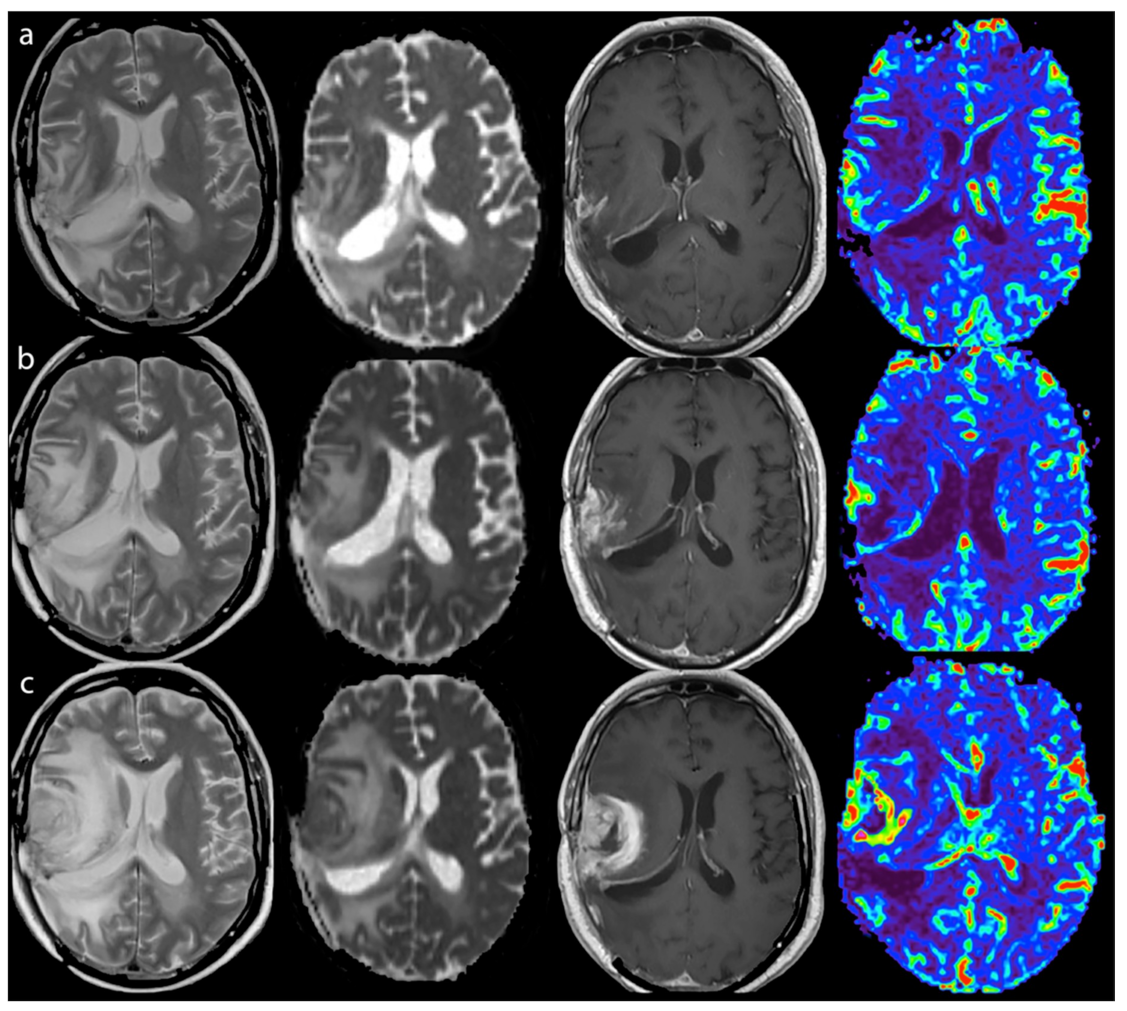

2.3.2. Perfusion

2.3.3. Diffusion

3.2.1. Response Assessment

3.2.2. Survival